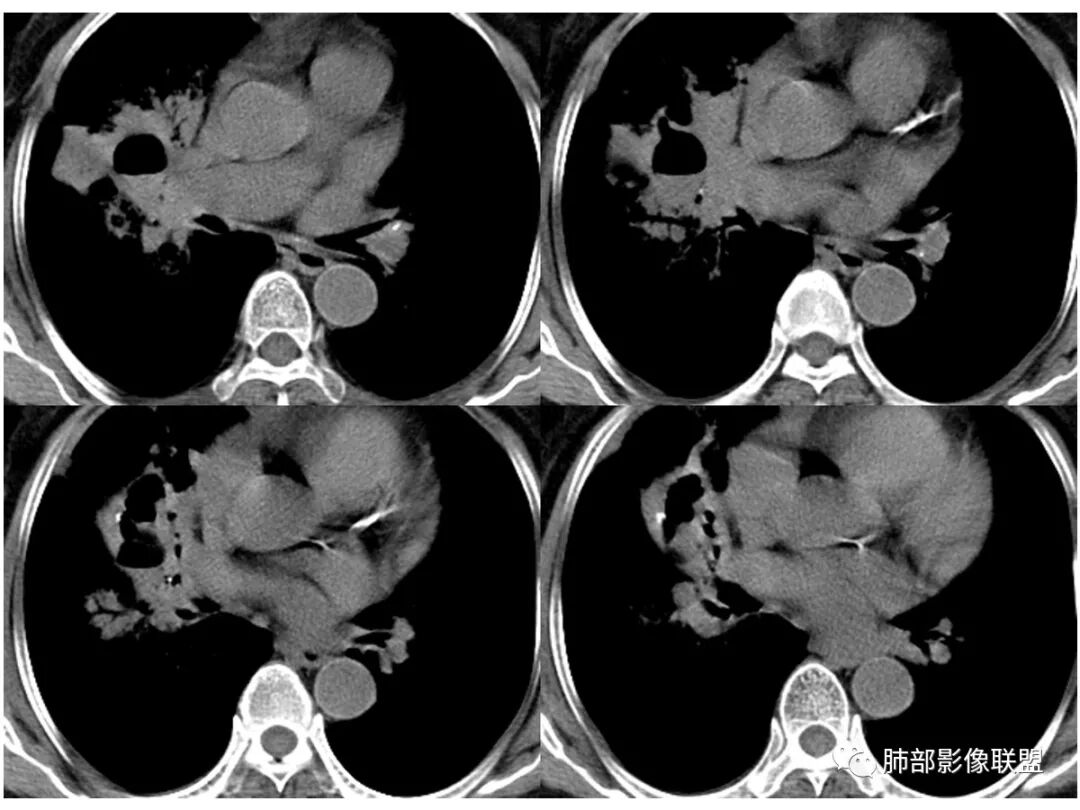

胸CT:右肺上叶实变内可见支气管充气征,近端支气管狭窄,远端扩张,周围可见毛玻璃影,右肺中叶支气管闭塞,并可见气道壁钙化,右肺中叶体积缩小,实变内可见空洞,并可见气液平面,空洞周围可见毛玻璃样影,右肺下叶支气管开口狭窄,右肺门淋巴结肿大。纵隔窗可见病灶与壁层胸膜间隙增宽,考虑良性病变-----感染性病变------TB?

右中叶支气管完全阻塞伴厚壁空洞,右上叶支气管不全阻塞伴大片GGN,右下部分GGN考虑腺鳞癌,结核待排。

老年女性,慢性病程,咳嗽伴白色粘液痰,无发热腹痛,糖尿病,白细胞及C反应蛋白不高,血沉快,铁蛋白高。胸部CT,右肺上叶大片状实变伴磨玻璃密度影,边界不清,边缘局部膨隆,叶裂弧形下坠,实变影宽基底与胸膜相贴;右肺下叶前基底段见类似病灶;右肺中叶不张并空洞形成,空洞内见气液平面;综合考虑右肺上叶及下叶肺炎型肺癌,右肺中叶结核。

这里是中叶的不张和空洞,有钙化,结核确实也不能排除

主病灶应该是粘腺腺癌,右中叶不张?,内空洞,壁光滑,考虑感染

3.熊老师告诉我们:肺结核可以有磨玻璃,这个我以前一直不知道,右肺门淋巴结有钙化,病灶内纵膈窗隐约细细点状钙化,所以结核磨玻璃可以,

纵隔窗,没有看到太多细支气管里粘液的密度。

中叶的体积缩小,也不是粘液腺癌能完全解释,